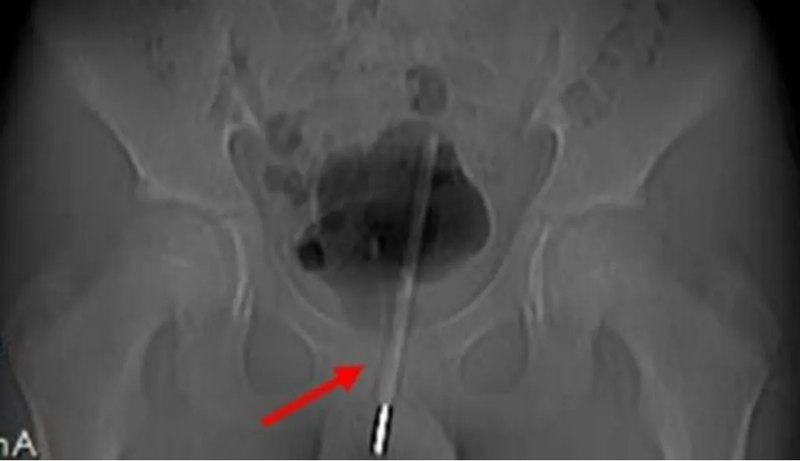

Los rayos x mostraron que se había introducido tanto el termómetro que le llegó hasta la vejiga

Sin embargo, el joven acabó sufriendo un intenso dolor durante nueve horas hasta que fue intervenido de urgencia ya que al parecer y según revelaron los rayos X, el termómetro había sido introducido muy adentro del tracto urinario, tanto que había llegado hasta la vejiga del niño.